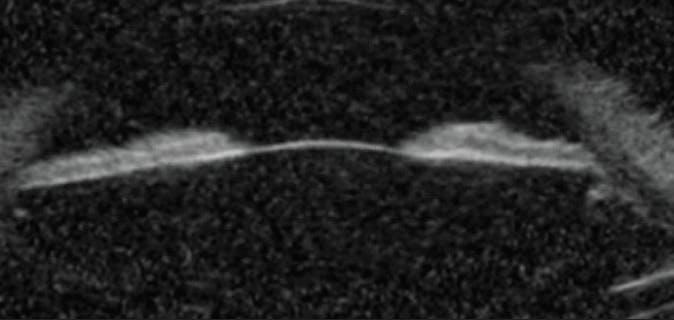

Upon examination, IOP was 14 mm Hg OD and 43 mm Hg OS. New visual field and optic nerve changes were consistent with moderate open-angle glaucoma (Figure 1). Ultrasound biomicroscopy did not demonstrate significant reverse pupillary block (Figure 2), and no iris transillumination defects were evident. Marked trabecular meshwork pigmentation was present in each eye, and a Krukenberg spindle was observed in the left eye. Pigment dispersion was therefore thought to be a factor in the IOP elevation.

Figure 1. Fundus perimetry shows moderate loss in the left eye’s visual field and a lid artifact in the right eye’s visual field. Fundus photography shows tilted myopic nerves and inferior thinning of the optic nerve in the left eye.